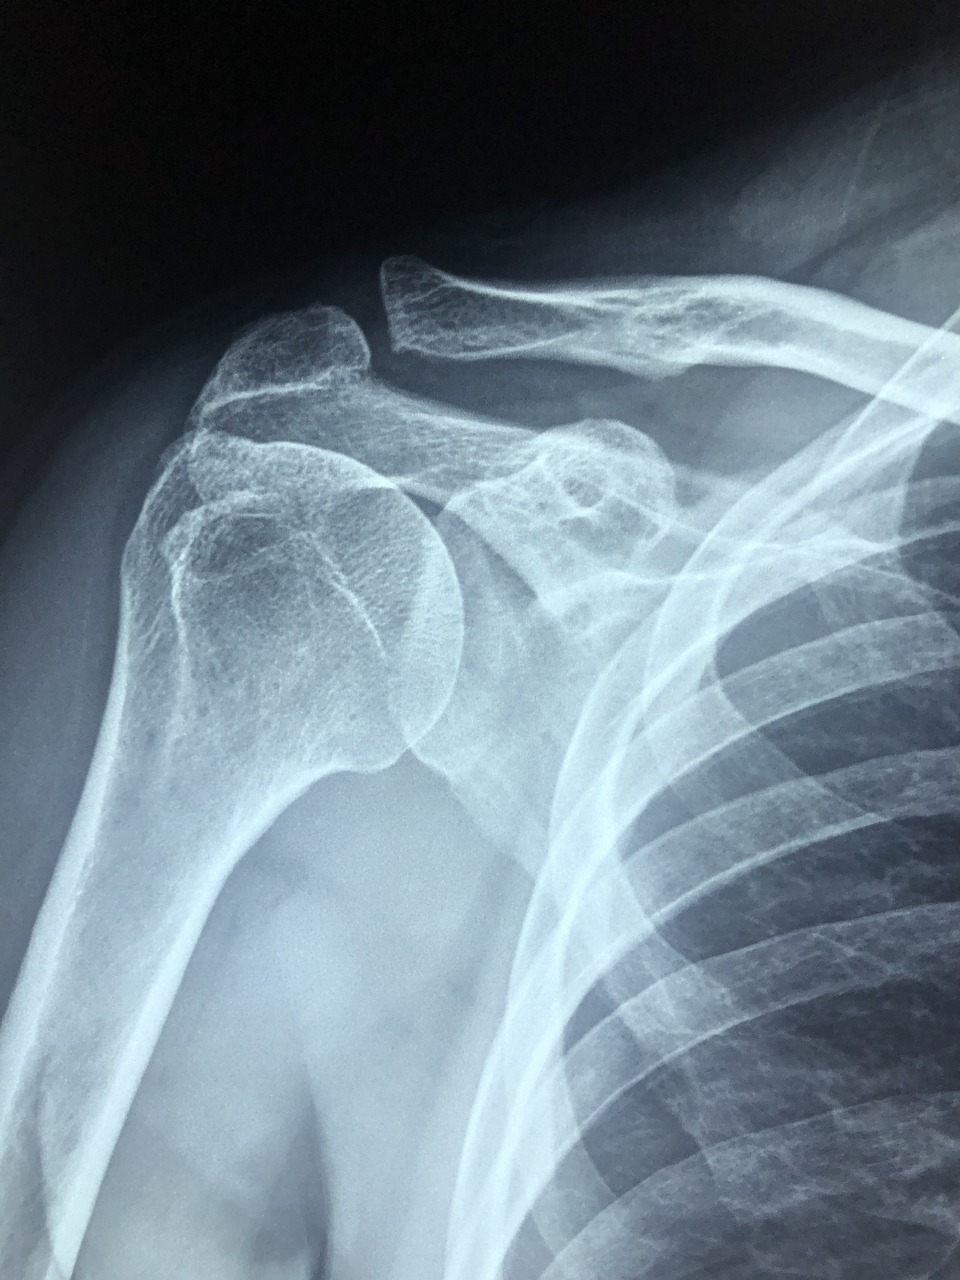

2) 영상 검사

- X선 : 뼈의 상태를 확인하기 위해 X-ray 촬영을 실시합니다. 오십견의 경우, 뼈에 이상이 있는지 확인하는 데 도움이 됩니다.